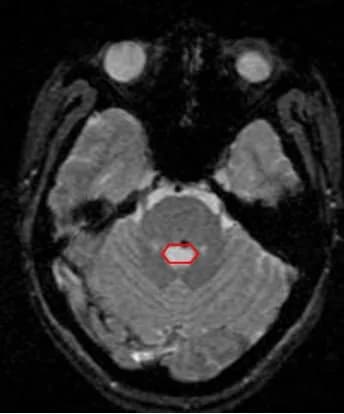

U máu thể hang: Một dị dạng mạch não

U Máu Thể Hang: Tổng Quan và Điều Trị

Bệnh lý dị dạng mạch máu là sự xuất hiện một tổ chức mạch máu hoặc tổn thương bất ...